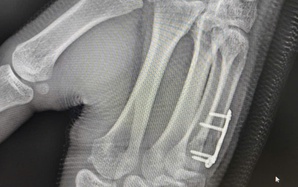

Giữ thang giúp hàng xóm, người đàn ông bị bỏng điện kinh hoàng

(NLĐO) - Bỏng điện do nổ hồ quang là tai nạn hiếm gặp nhưng cực kỳ nguy hiểm, có thể gây tổn thương sâu, lan rộng và đe dọa tính mạng chỉ trong tích tắc.